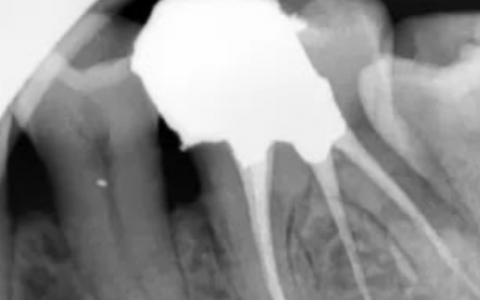

补牙,即医生所说的充填术,是治疗蛀牙的有效方法。蛀牙早期不痛不痒,直接补牙简单便宜效果好,拖到晚期就会出现各种疼痛不适,需要更复杂的根管治疗,甚至拔牙后种植,严重影响我们的生活和心情,而且需要花费更多的人力财力。